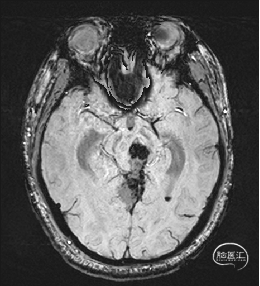

术前MRI检查

术前MRI检查提示左侧丘脑中脑海绵状血管瘤并卒中,梗阻性脑积水;

年轻患者,较短时间内发生左侧丘脑二次出血,出现右侧面部及上肢麻木,复视,第二次出血后并发梗阻性脑积水,出现头痛。结合病史、神经系统体征、头颅CT及MRI检查,诊断左侧丘脑及中脑CM并卒中、脑积水明确,并导致了神经功能障碍,具备手术指征。

脑积水导致的颅内高压,幕下小脑上通路更为狭小,大脑大静脉复合体的显露及分离困难增大;

根据MRI及DTI显示,只有在丘脑与上丘之间的点(dot)进入病变才可能在切除病变时最大程度保护神经功能,由于上述原因,该“点”在术中显露极其困难,虽有导航指引,电生理监测的条件下,对术者的耐心、技术、经验及体能依然是极大的挑战;